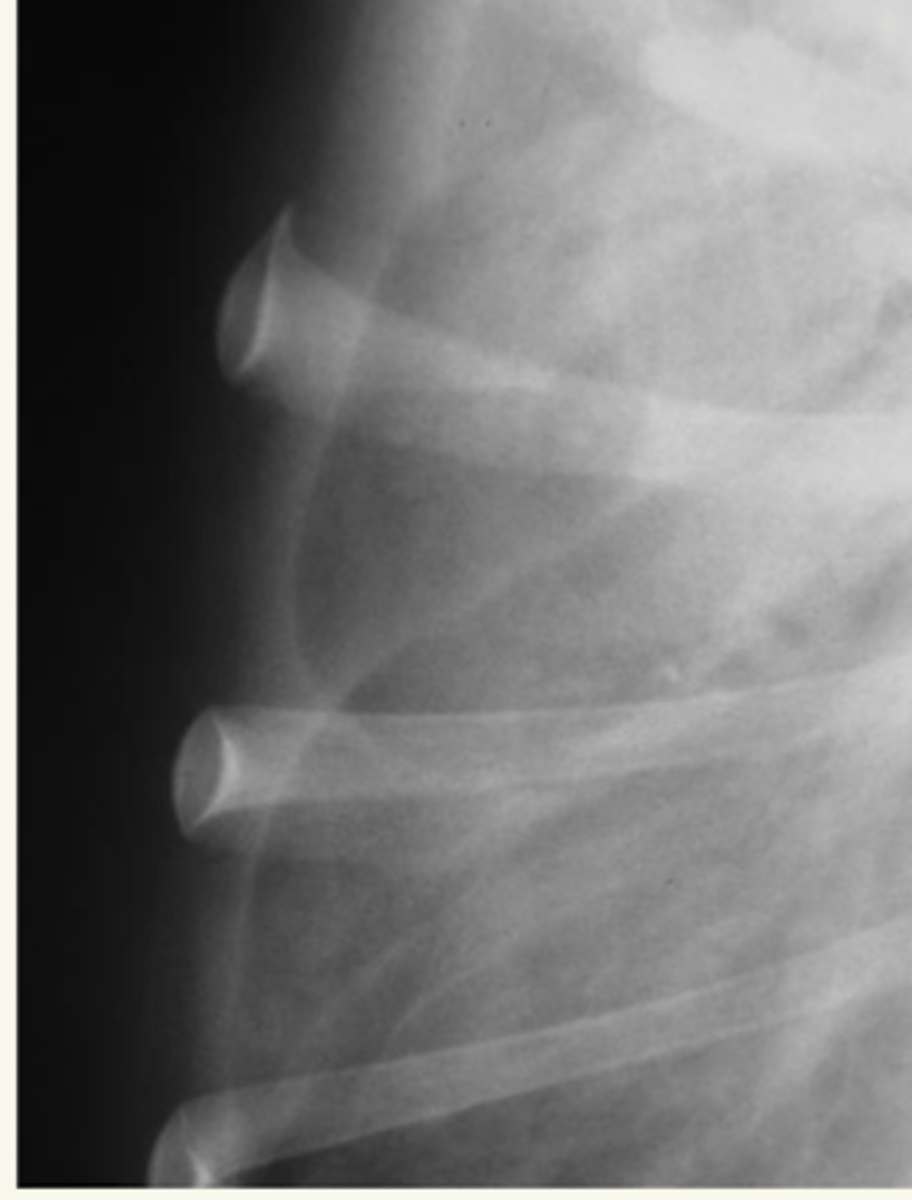

pneumotorax

patología:

patolgía